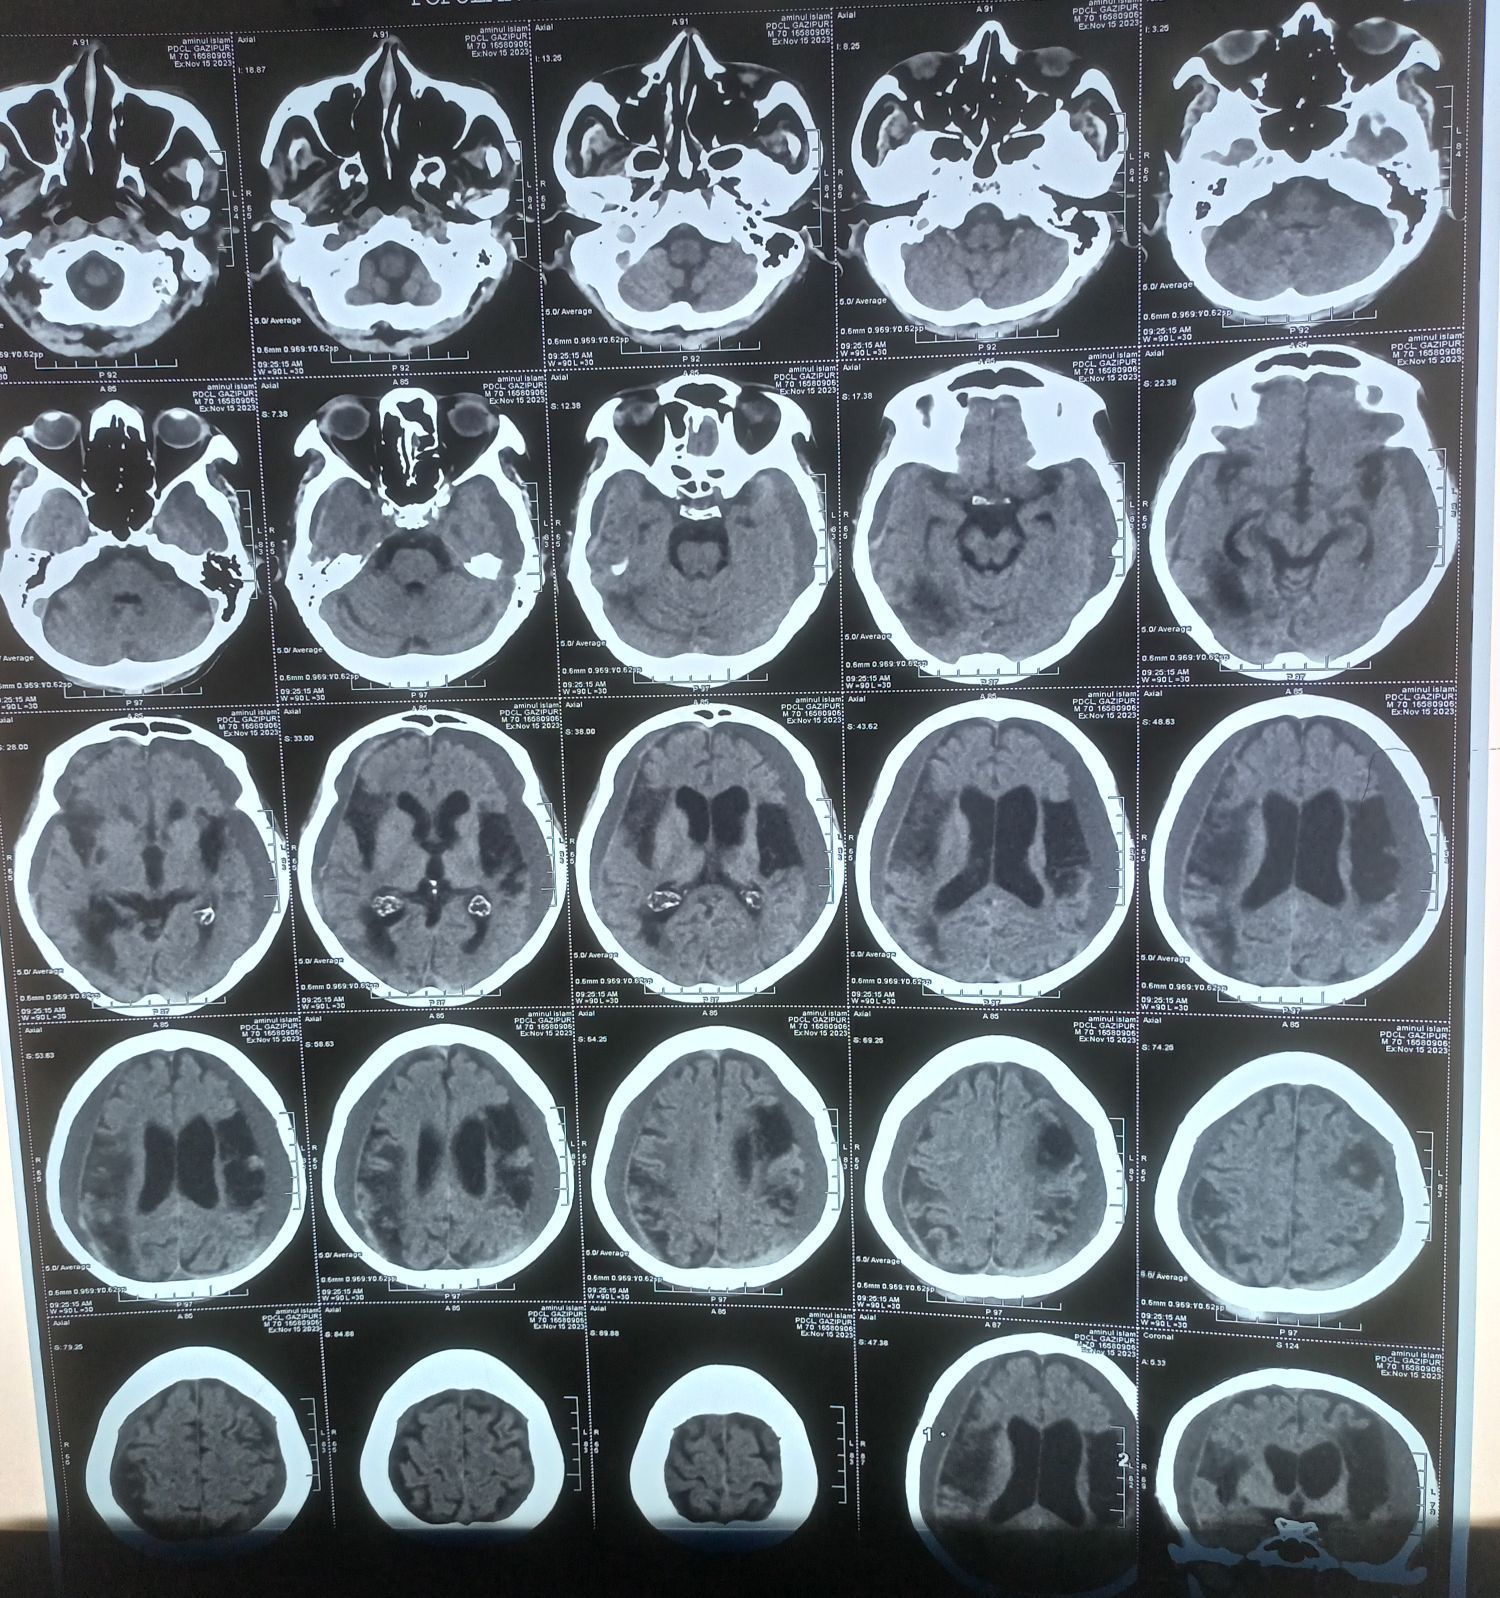

An interesting CT Brain finding

A 60 years old man having traumatic head injury following RTA.